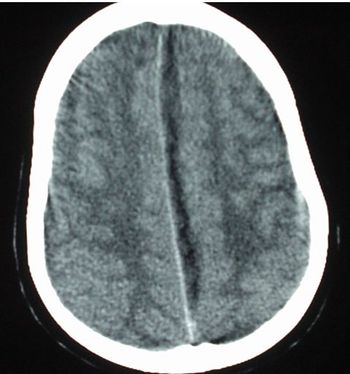

Cold symptoms that persisted for several weeks became ominous signs when the headache worsened and walking became difficult.

The patient denies vertigo, hearing change, headache or ear pain. Physical exam and past medical history are benign. What does the brain MRI tell you?

Signs and symptoms may raise suspicion for a posterior circulation stroke.